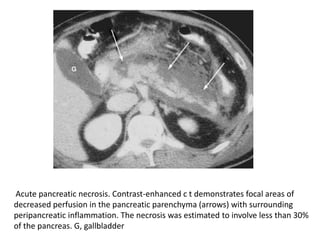

Acute pancreatic necrosis. Contrast-enhanced c t demonstrates focal areas of

decreased perfusion in the pancreatic parenchyma (arrows) with surrounding

peripancreatic inflammation. The necrosis was estimated to involve less than 30%

of the pancreas. G, gallbladder